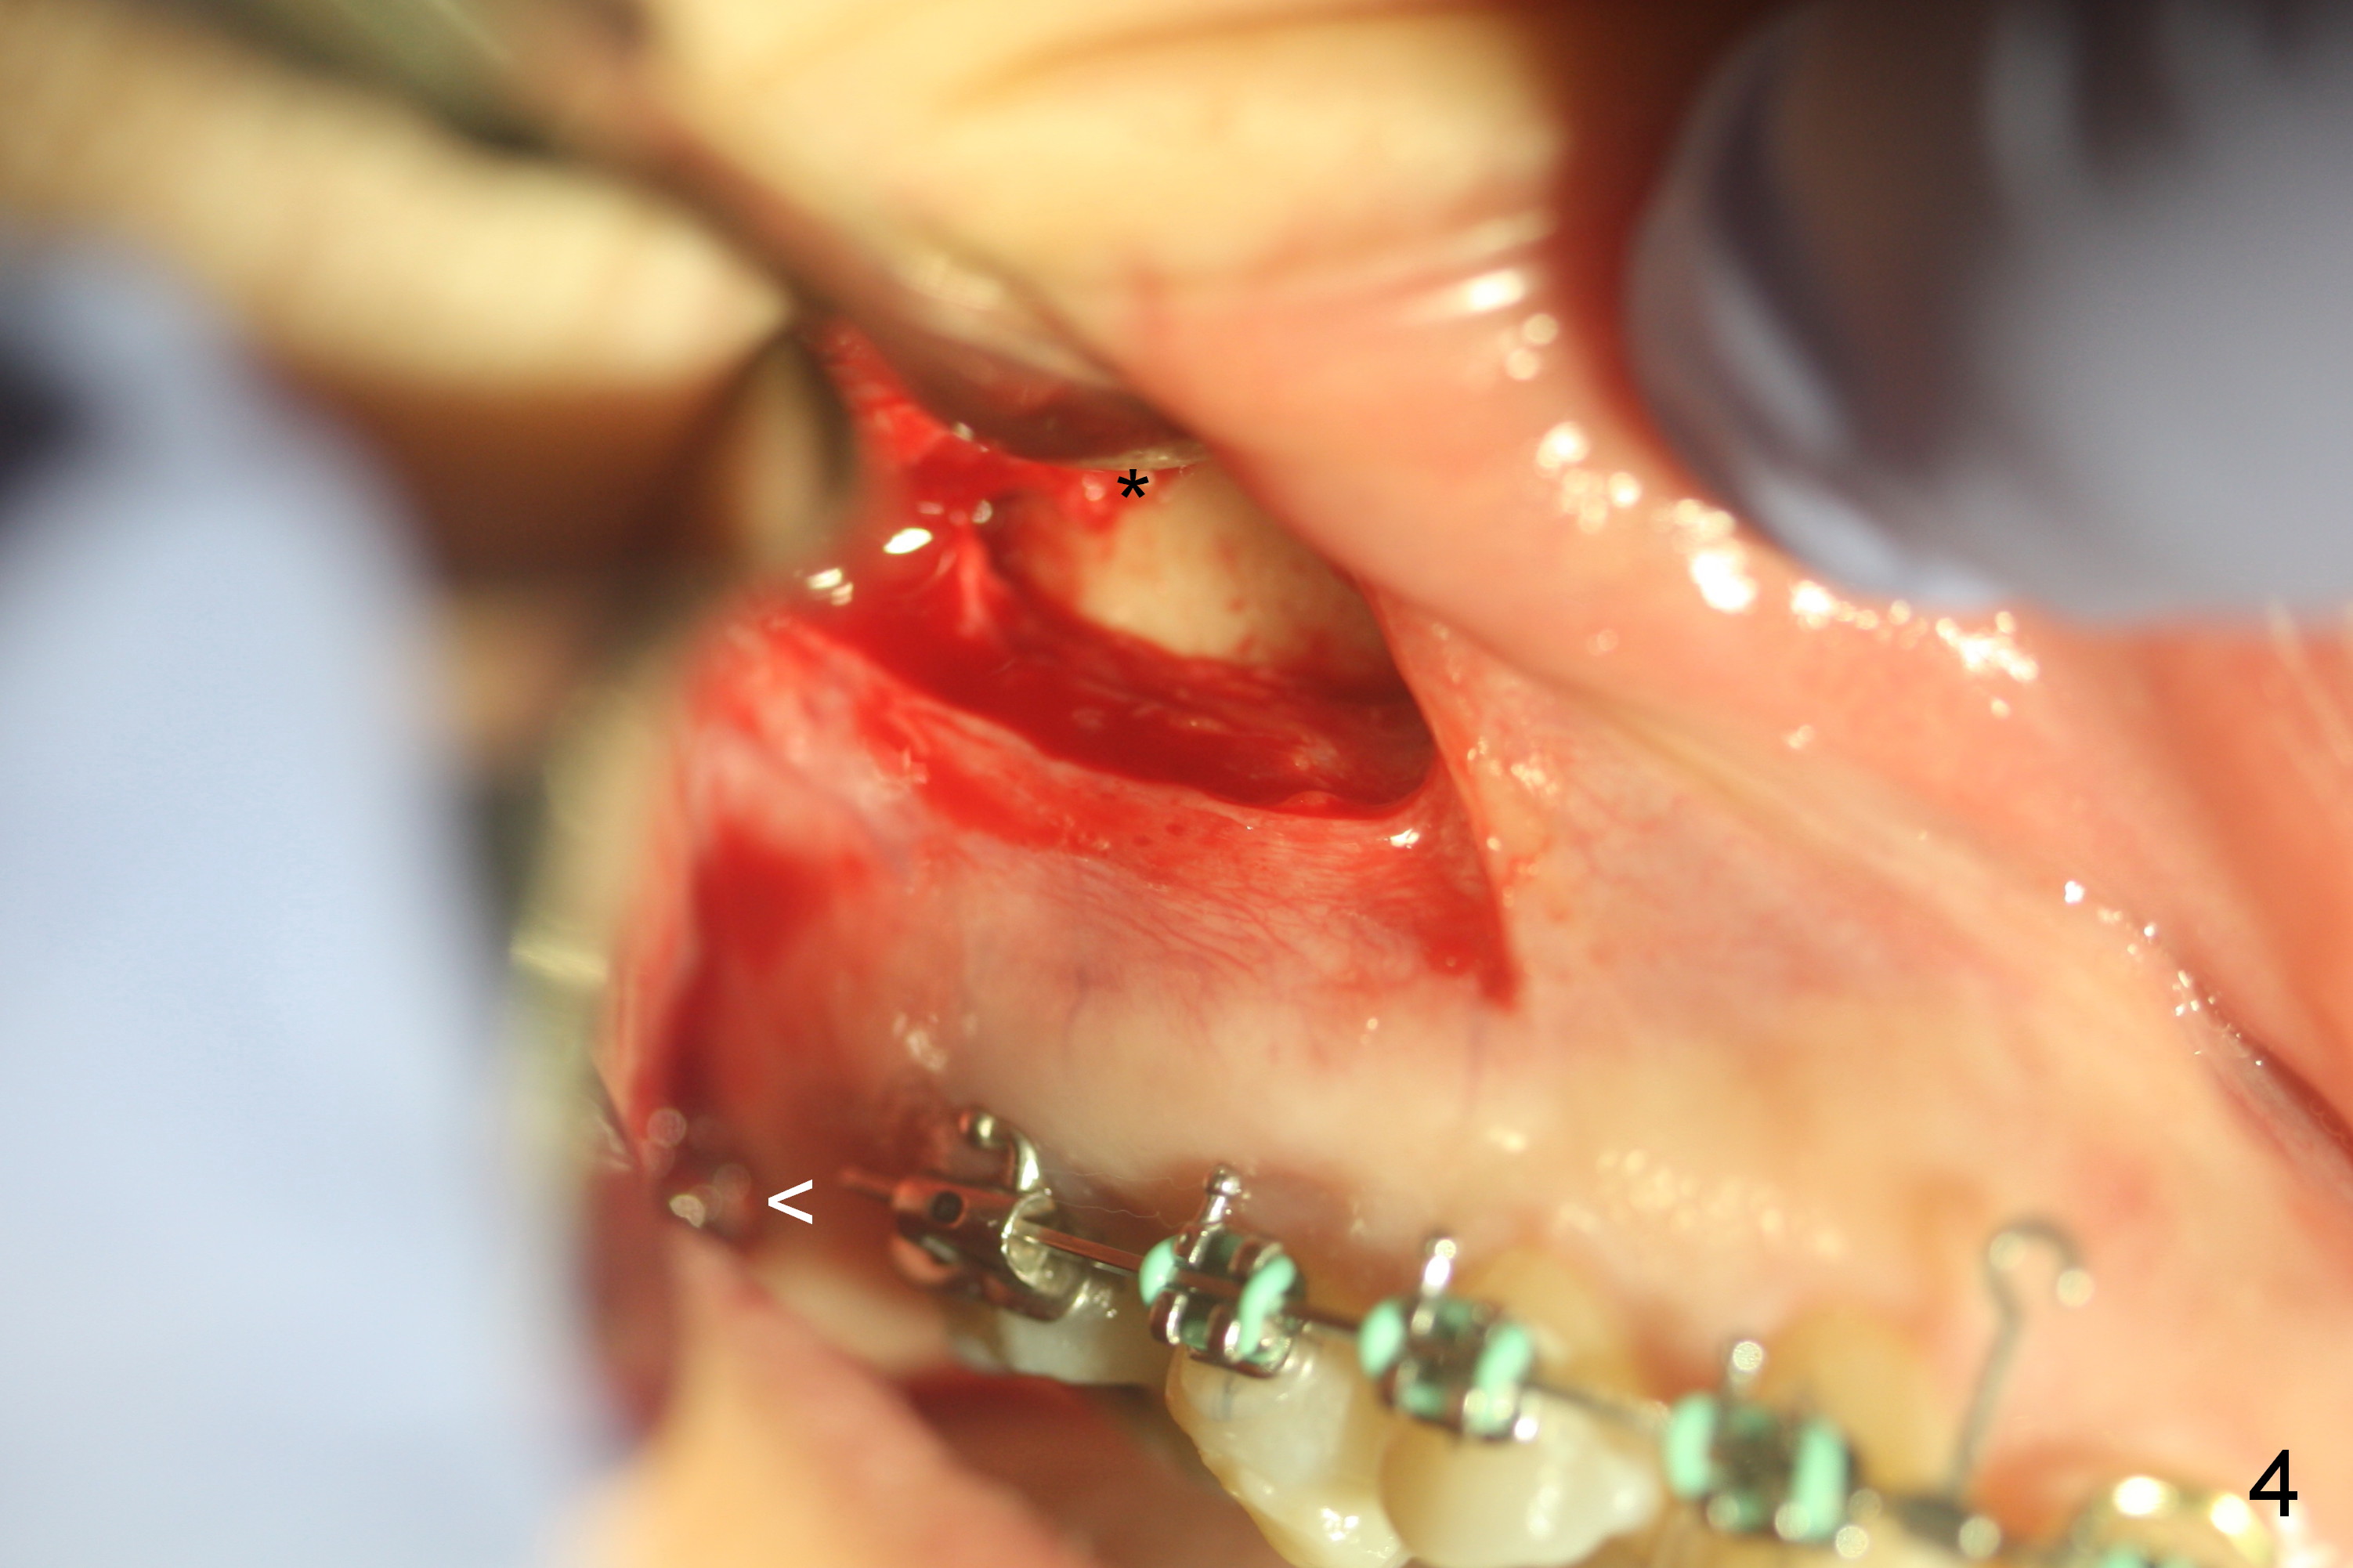

6. Incision is made 4-5 mm above the mucogingival junction, over the maxillary 1st molar (Fig.3 *)

7. Rationale: the Zygomatic mini implant (Fig.4 *) will be placed higher than the existing one (<)